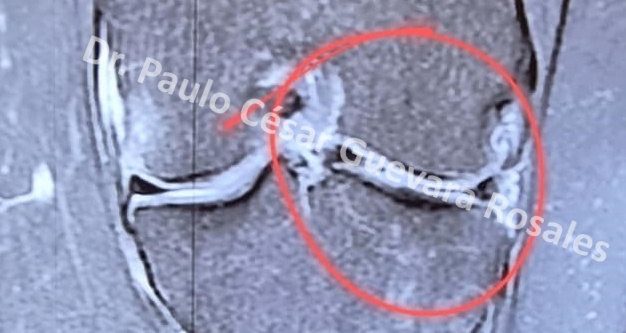

Lesión en asa de balde del menisco lateral variedad luxada, no reciente.

Reinserción anatómica con estimulación capsular

y suturas all inside , S&N fast fix* y Arthrex Meniscal cinch II*.